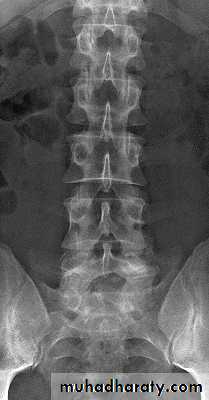

Lumbar Spine X Ray

Lateral radiograph

A/P radiograph• Sacrum

X-rays The anteroposterior x-ray may show loss of

height or splaying of the vertebral body with a crush

fracture

Severe axial compression may ‘explode’ the vertebral body, causing failure of both the anterior and the middle columns. The posterior column is usually, but notalways, undamagedAnteroposterior x-rays may show

spreading of the vertebral body with an increase of the interpedicular distance